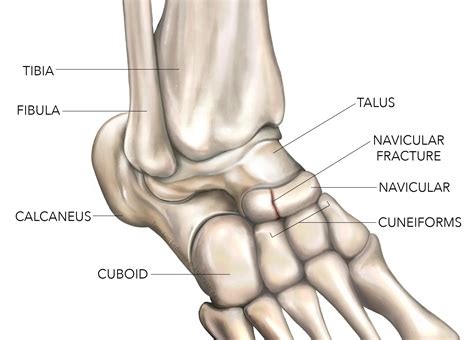

The scaphoid is a peanut-shaped bone located on the thumb side of your wrist, just above the radius. It plays a significant role in how your wrist moves, acting as a bridge between the two rows of carpal bones. What makes this injury particularly tricky is the bone's unique blood supply. Blood flows into the scaphoid from the distal end toward the proximal end. When a fracture occurs, the blood supply to part of the bone can be disrupted, significantly hindering the natural healing process.

Diagnosis usually involves a physical examination followed by imaging. X-rays are the first line of defense; however, because scaphoid fractures can be hairline, they are not always visible on initial X-rays. If your doctor suspects a fracture but the image is clear, they may order an MRI or a CT scan to confirm the injury.

Because the scaphoid is susceptible to poor blood flow, there is a risk of a condition called avascular necrosis, where the bone tissue dies due to lack of blood. Another concern is non-union, where the bones fail to heal, leading to pain and weakness. If you notice a sudden increase in pain, numbness in your fingers, or if the swelling does not go down after several weeks, contact your specialist immediately to ensure your Scaphoid Fracture Treatment is still on track.